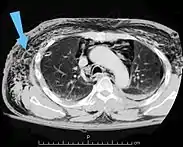

من السهل تشخيص الحالات الكبيرة من نفاخ تحت الجلد بسبب العلامات المميزة لهذه الحالة.[1] في بعض الحالات، تكون العلامات خفية مما يجعل التشخيص أكثر صعوبة.[11] يُستَخدم التصوير الطبي لتشخيص الحالة أو لتأكيد التشخيص السريري. في الصورة الإشعاعية الصدرية، قد يظهر نفاخ تحت الجلد كحزوزٍ إشعاعيةٍ شفافة في النمط المتوقع لمجموعة العضلات الصدرية الكبرى. قد يتداخل الهواء في الأنسجة تحت الجلدية مع التصوير الإشعاعي للصدر، مما يُخفي حالاتٍ خطيرة مثل استرواح الصدر.[26] قد يقلل أيضًا من فعالية الموجات فوق الصوتية في الصدر.[27] من ناحية أخرى، بما أن نفاخ تحت الجلد قد يظهر بوضوح في الأشعة السينية للصدر قبل أن يحدث استرواح الصدر، يمكن استخدام وجوده للدلالة على حدوث الإصابة الأخيرة.[11] يمكن رؤية النفاخ تحت الجلد أيضًا في الأشعة المقطعية، حيث تظهر تجمعات الهواء تحت الجلد كمساحاتٍ مظلمة. يُعتبر التصوير المقطعي دقيق جدًا، حيث يجعل من السهل العثور على البقعة الدقيقة التي يدخل منها الهواء إلى الأنسجة الرخوة.[11] في عام 1994، نشر ماكلين مزيدًا من الأفكار حول الفيزيولوجيا المرضية لمتلازمة ماكلين التلقائية، والتي تحدث نتيجة لنوبةٍ حادةٍ من الربو.